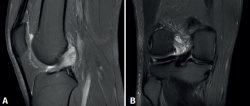

En ambos pacientes se realizó anestesia raquídea para realizar la cirugía y se utilizó manguito de isquemia a nivel del muslo. Se colocó al paciente en decúbito supino, utilizando un soporte en U en el tercio distal del muslo para la fijación de la extremidad. Se realizaron los portales artroscópicos habituales anterolateral y anteromedial, objetivando en la exploración diagnóstica de la rodilla la presencia de un ganglión localizado en el fascículo posterolateral del LCA (Figura 3) que, cuando se realizaban los movimientos de flexión y en posición de cuatro, se pinzaba en el espacio articular tibiofemoral externo. Para realizar la resección artroscópica del quiste se colocó al paciente en la posición “de cuatro”, facilitando la diferenciación anatómica de los fascículos anteromedial y posterolateral del LCA, tal y como proponen Hopper G et al.(4). Se realizó la disección y exéresis cuidadosa del quiste con una pinza basket, un terminal shaver de 4 mm y un terminal de ablación por radiofrecuencia (Figura 4). Al finalizar la resección del quiste, se realizó una nueva exploración dinámica de la rodilla, donde se evidenció la ausencia de pinzamiento entre el LCA, el cóndilo femoral y el platillo tibial lateral, a la vez que se comprobó la estabilidad del remanente del LCA (Figura 5).

Figura 4. Visión artroscópica desde el portal anterolateral. Se introduce a través del portal anteromedial el instrumental. A: inicio del desbridamiento del quiste con un basket artroscópico; B: se continúa el desbridamiento del quiste con un shaver de 4 mm respetando las fibras del ligamento cruzado anterior sano.

En el postoperatorio se autorizó la movilidad y la carga progresiva con bastones según la tolerancia. En ambos pacientes la sintomatología dolorosa y las restricciones de movilidad articular se resolvieron completamente. No se realizó RM de control en ninguno de los dos casos.

reaca.32385.fs2409018-figura5.png

Figura 5. Visión artroscópica desde el portal anterolateral. A: tras el desbridamiento se observa que no existe pinzamiento del espacio articular femorotibial lateral en posición “de cuatro” a 90° de flexión; B: palpación de la tensión del remanente del ligamento cruzado anterior.